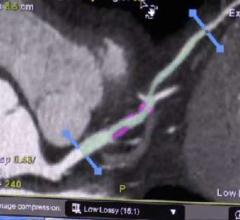

June 30, 2016 — Vital Images Inc. recently launched version 7 of its Vitrea advanced visualization software. This ...

Here is a recap of some of the top trends and new technology at the Society of Cardiovascular Computed Tomography (SCCT) ...

DAIC Editor Dave Fornell shares some of the most innovative new technologies shown on the expo floor and discusses in ...